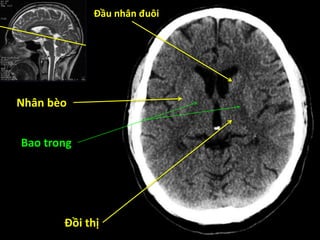

Đầu nhân đuôi

Đồi thị

Nhân bèo

Bao trong

Bèo sẫm

Cầu nhạt

Thùy đảo

Đầu nhân đuôi Đồithị Nhân bèo Bao trong

Đầu nhân đuôi Bèosẫm Cầu nhạt Thùy đảo Cánh tay trước bao trong